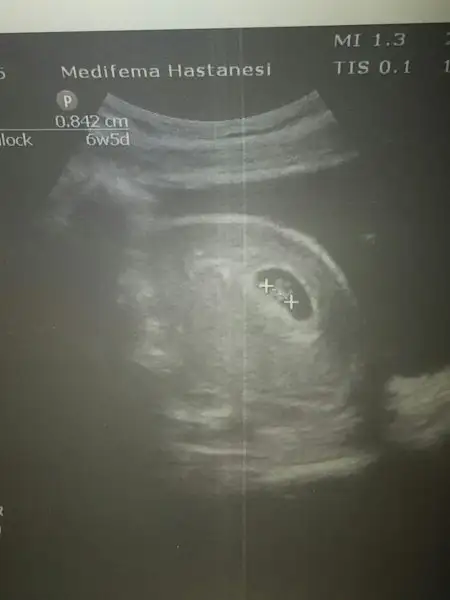

Merhaba cnm benimkinide yorumlarmisin.usg karindan